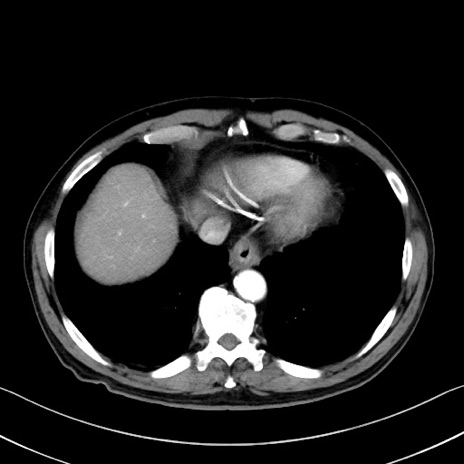

症例35(横断像)

冠状断像

【症例】70歳代 男性

【主訴】腹部膨満、嘔吐

【現病歴】昨日より腹部膨満感出現。本日増悪し、仙痛出現。嘔吐あり、受診。

【既往歴】糖尿病、胆摘後

【身体所見】BP 149/80mmHg、HR 74/min、BT 35.9℃、腹部:膨満、軟、圧痛なし。腸雑音減弱あり。上腹部正中切開瘢痕あり。

【データ】WBC 13500、CRP 1.72